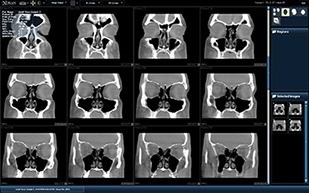

The sinuses, ears, facial bones, and Temporomandibular Joints TMJ’s can be displayed clearly and in various views which allow us to scan, diagnose, and treat within a single visit.

The MiniCAT™ is a compact, low radiation dose CT scanner specifically

designed to scan the sinuses and temporal bones.